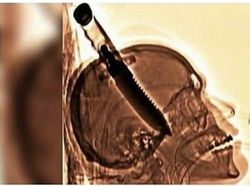

Pada tahun 1998, Michael Hill ditikam di tengkoraknya, oleh orang tak dikenal, dengan pisau besar untuk bertahan hidup ketika dia membukakan pintu di rumah temannya. Dia bertahan hidup bahkan tanpa infeksi dan mendapatkan kembali kesadaran dan seluruh fungsi tubuhnya dalam waktu seminggu, meskipun pisau tersebut telah menyebabkan kerusakan permanen pada ingatannya dan melumpuhkan tangan kirinya. Foto: Instagram/@horrorsfs